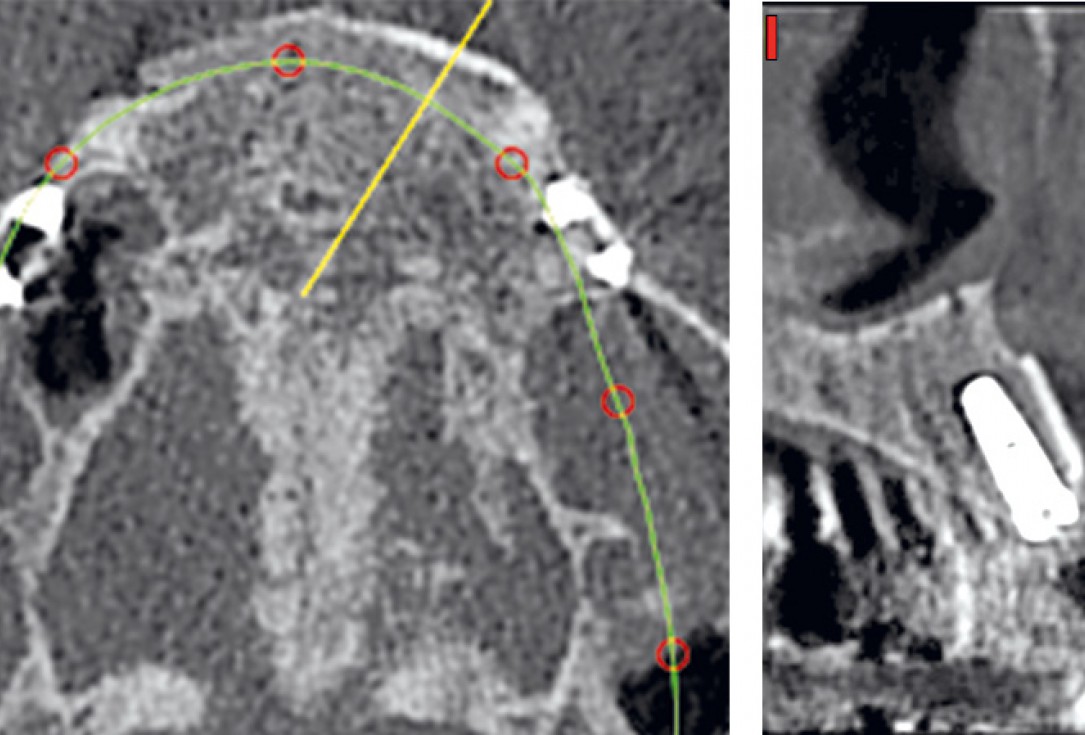

03 / 22 - Initial situation – CBCT image of the first quadrant

04 / 22 - Initial situation – CBCT image of the second quadrant